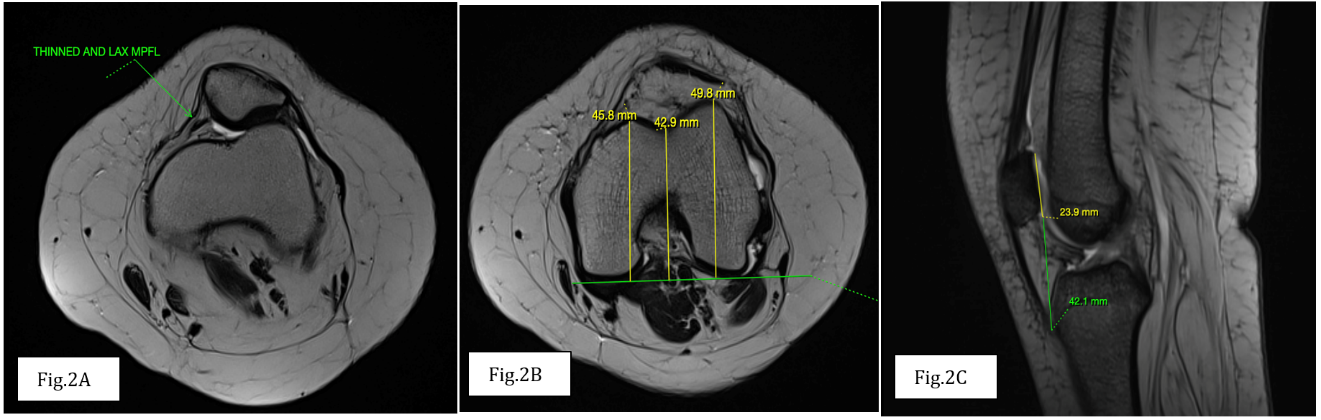

An 18-year-old female with a known history of congenital talipes equinovarus since birth presented with recurrent dislocations of the left patella, which had been occurring since childhood. MRI of the left knee showed a lateral trochlear inclination angle and trochlear groove depth within normal limits. The trochlear facet asymmetry ratio was >0.4, and the sulcus angle was borderline increased at <145°. There was no evidence of supratrochlear spur or prominence. The modified Insall–Salvati index was below 2, ruling out patella alta. The TT-TG distance measured approximately 14.5 mm, which is within the normal range. The MPFL appeared thin and wavy but was intact. Lateral patellar subluxation was present (Fig 2). These findings point toward a diagnosis of patellar instability due to soft tissue (MPFL) laxity in the absence of osseous dysplasia, likely influenced by the patient’s background of congenital limb deformity.

Figure 2: (a) Axial T2 weighted image showing thinned and lax medial patello-femoral ligament. (b) Axial T2 weighted image showing normal trochlear depth i.e., >3 mm. (c) Sagittal T2 gradient echo sequence showing normal modified Insall-Salvati ratio <2.